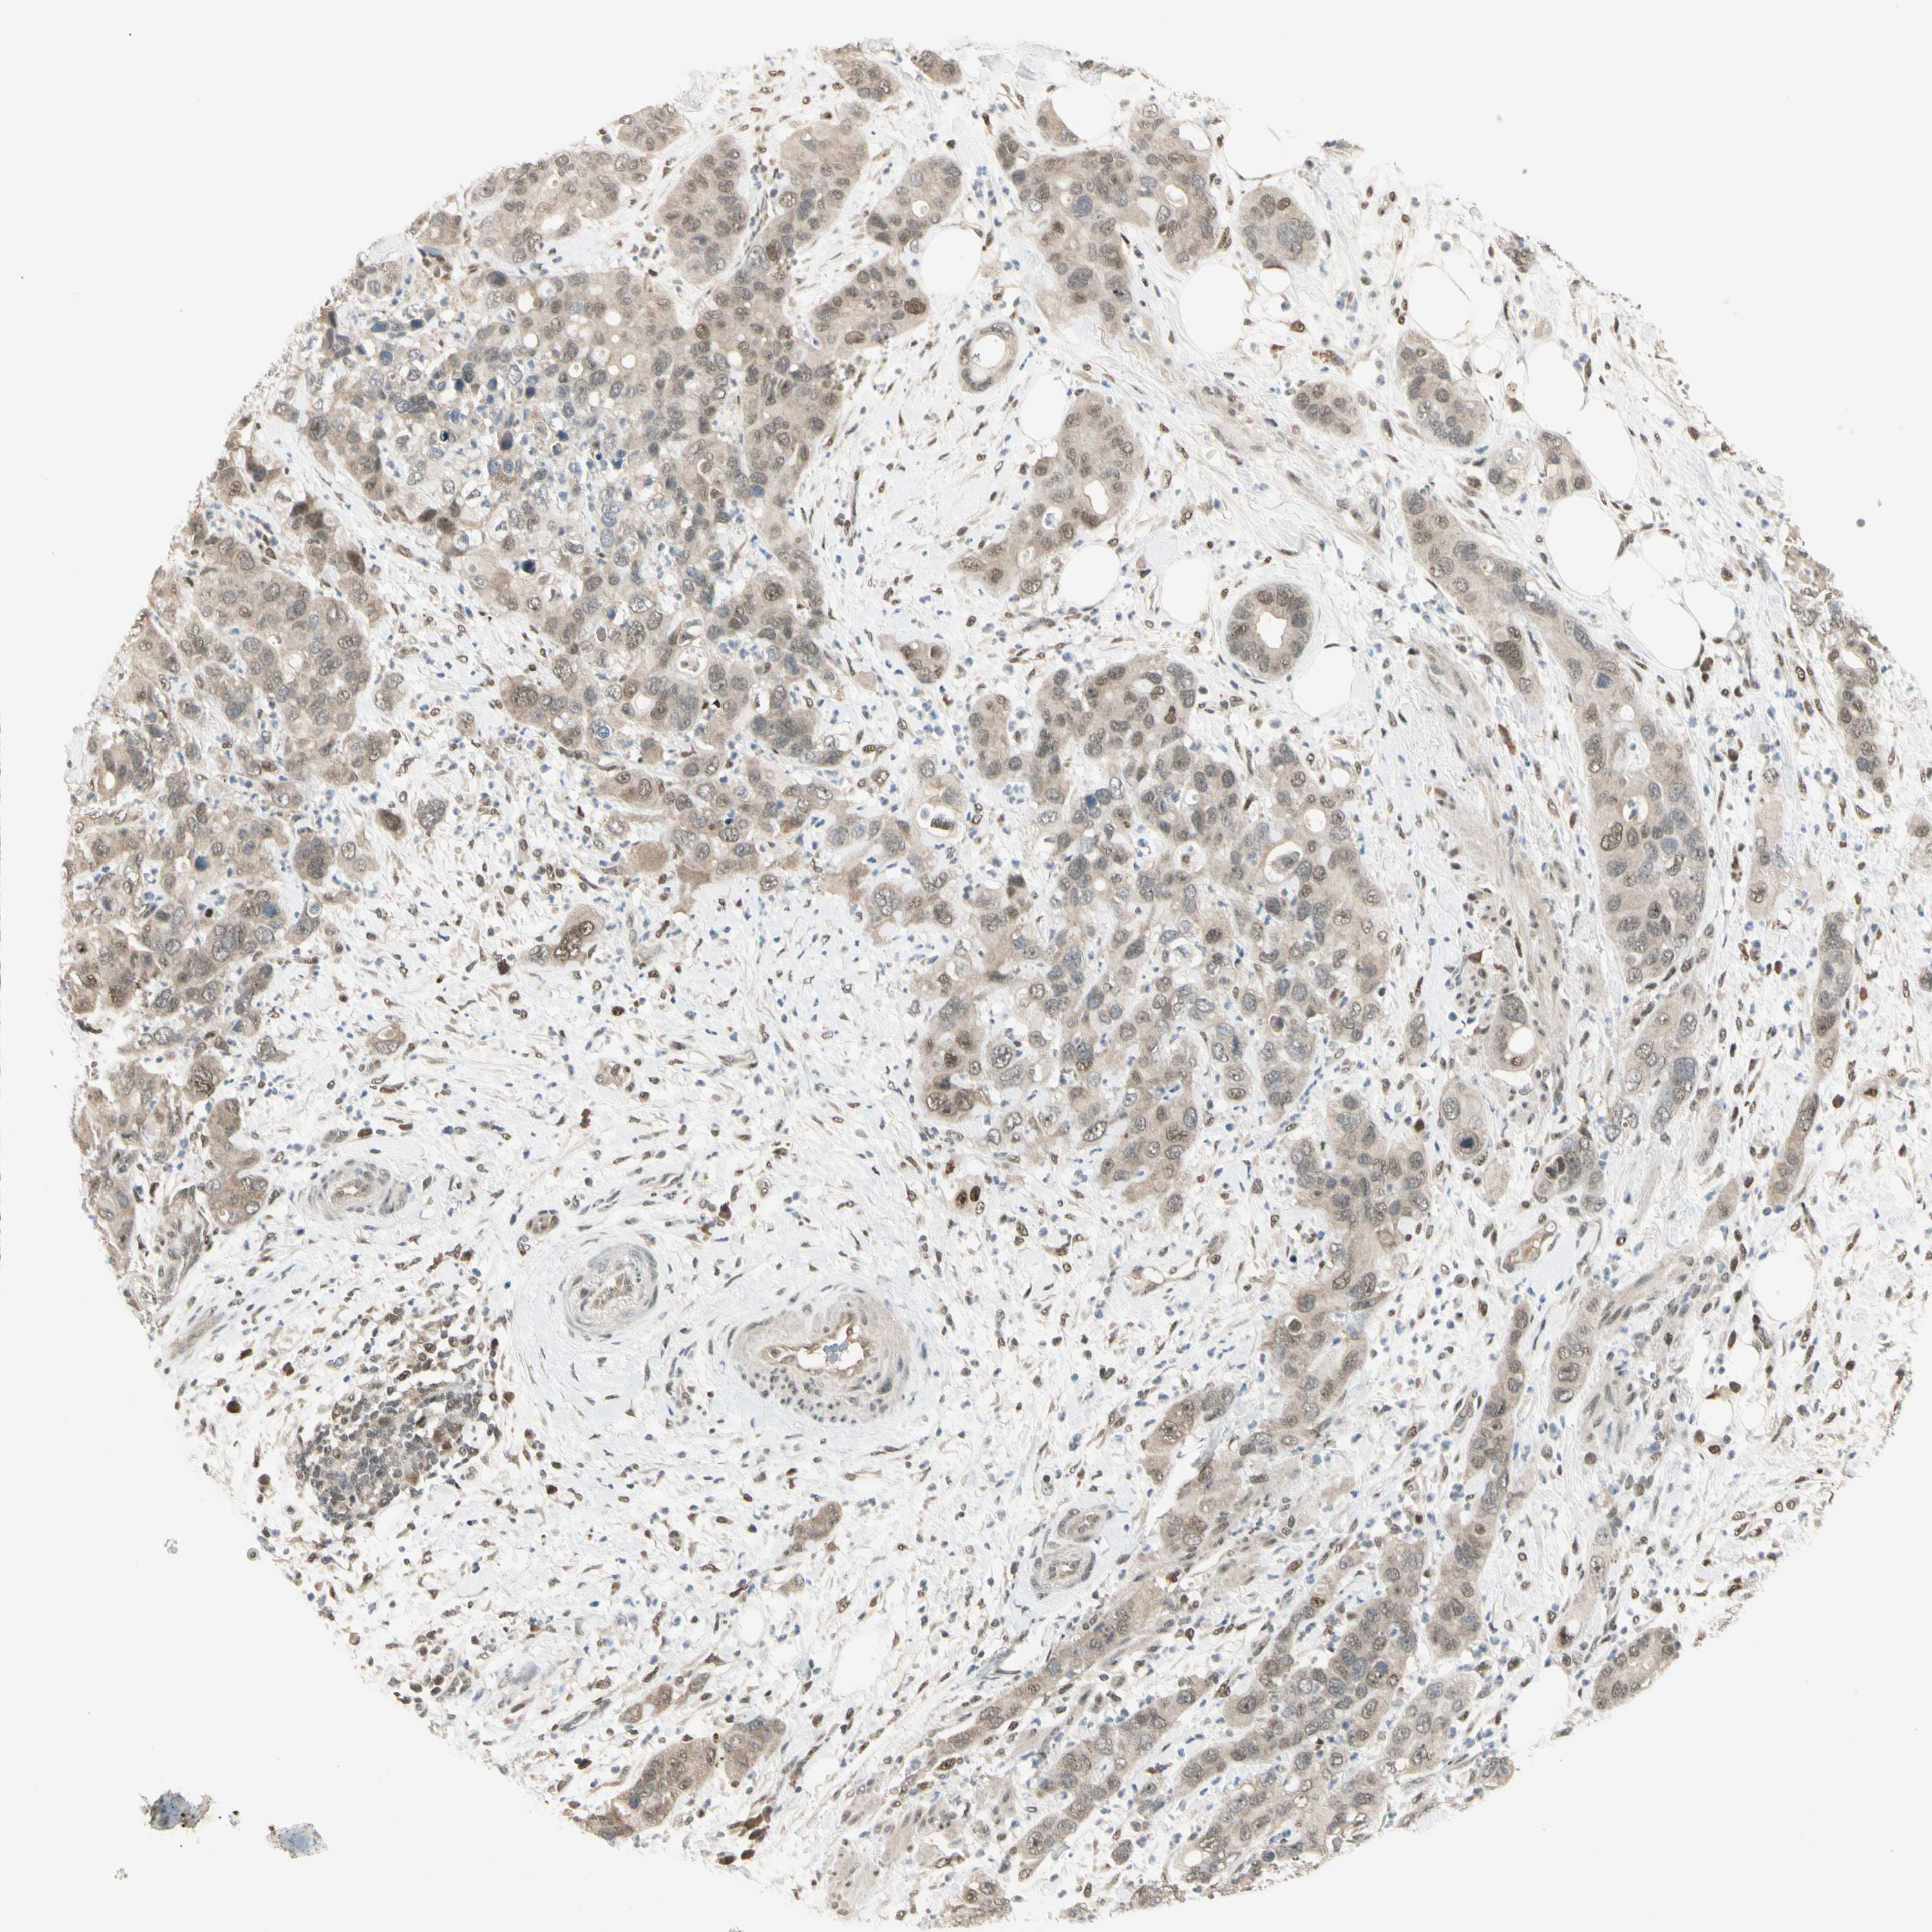

PANCREATIC CANCER - Protein expressioni

A mouse-over function shows sample information and annotation data. Click on an image to view it in a full screen mode. Samples can be filtered based on level of antibody staining by selecting one or several of the following categories: high, medium, low and not detected. The assay and annotation is described here.

Note that samples used for immunohistochemistry by the Human Protein Atlas do not correspond to samples in the TCGA dataset.

Antibody stainingi

Antibody staining in the annotated cell types in the current human tissue is reported as not detected, low, medium, or high, based on conventional immunohistochemistry profiling in selected tissues. This score is based on the combination of the staining intensity and fraction of stained cells.

Each image is clickable and will lead to virtual microscopy that enables deeper exploration of all samples and also displays staining intensity scores, fraction scores and subcellular localization as well as patient and tissue information for each sample.

Antibody HPA007990

Staining

High

Medium

Low

Not detected

Intensity

Strong

Moderate

Weak

Negative

Quantity

>75%

75%-25%

<25%

None

Location

Nuclear

Cytoplasmic/membranous

Cytoplasmic/membranous,nuclear

Adenocarcinoma, NOS